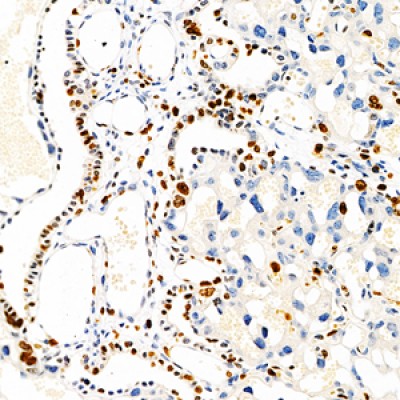

| IHC analysis of ki67 (GB111141). Sample: Mouse placenta (Paraffin), 4% PFA (G1101) 12-24h. Antigen retrieval: Citrate buffer (pH 6.0) (G1201), pressure cooker 2min. Blocking buffer: 3% BSA in PBS (GC305010), RT, 30min. Primary antibody: 1: 1000, 4°C overnight. Secondary antibody: HRP Goat Anti-Rabbit lgG (GB23303), 1: 200 RT 1h. |